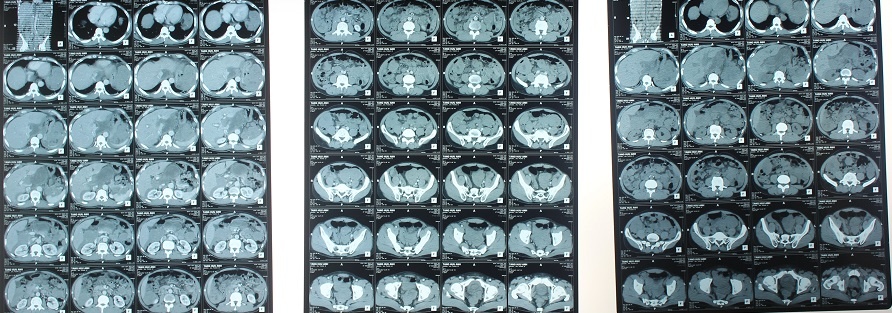

| Hình ảnh chụp hàng trăm khối u chiếm phần lớn ổ bụng bệnh nhân. Ảnh: Bác sĩ cung cấp. |

Kết quả xét nghiệm và chụp chiếu cho thấy có những khối u xuất phát từ thân vị xâm lấn lách, kích thước lớn nhất 13x8 cm, ngoài ra nằm rải rác khắp ổ bụng với rất nhiều u kích thước, trong đó có một số khối u gây tắc ruột non, ổ bụng có dịch.